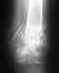

В декабре 2014 года был открытый оскольчатый перелом обеих костей правой голени в с\3-н\3 со смещением отломков.

Был выполнен остеосинтез правой большеберцовой кости метафизарной пластиной фирмы Синтес. Сейчас , через 6 месяцев после операции, даю полную нагрузку на ногу, но передвигаюсь с помощью трости, поскольку есть боль при движении. Также визуально видно искривление и утолщение в районе лодыжки. Долгая ходьба (с одной канадской тростью) также вызывает сильные болезненные ощущения. Врач предлагает операцию, но не говорит конкретно какую. Правильно ли я понимаю, что определить вариант действий можно только уже на операционном столе? Волнуюсь, что вскроют ногу, удалят пластину, а деформацию устранить не смогут. Применим ли в этом случае аппарат Илизарова? БИОС?

• Кликните для загрузки файла 29.05.15_2.JPG

Да, тут нужна хирургическая коррекция. Какой именно технический вариант предпочесть, одномоментно или постепенно исправить - какого-то универсального ответа нет. Выбор аависит от знаний и умений конкретного специалиста и возможностей клиники. У нас такого рода коррекций выполняется много, едут из разных мест.